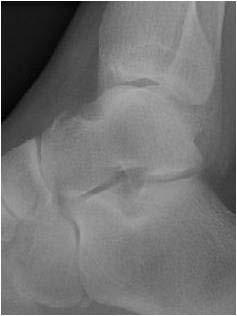

You have had a simple soft tissue injury to your ankle/foot, as part of this you may also have a chipped bone.